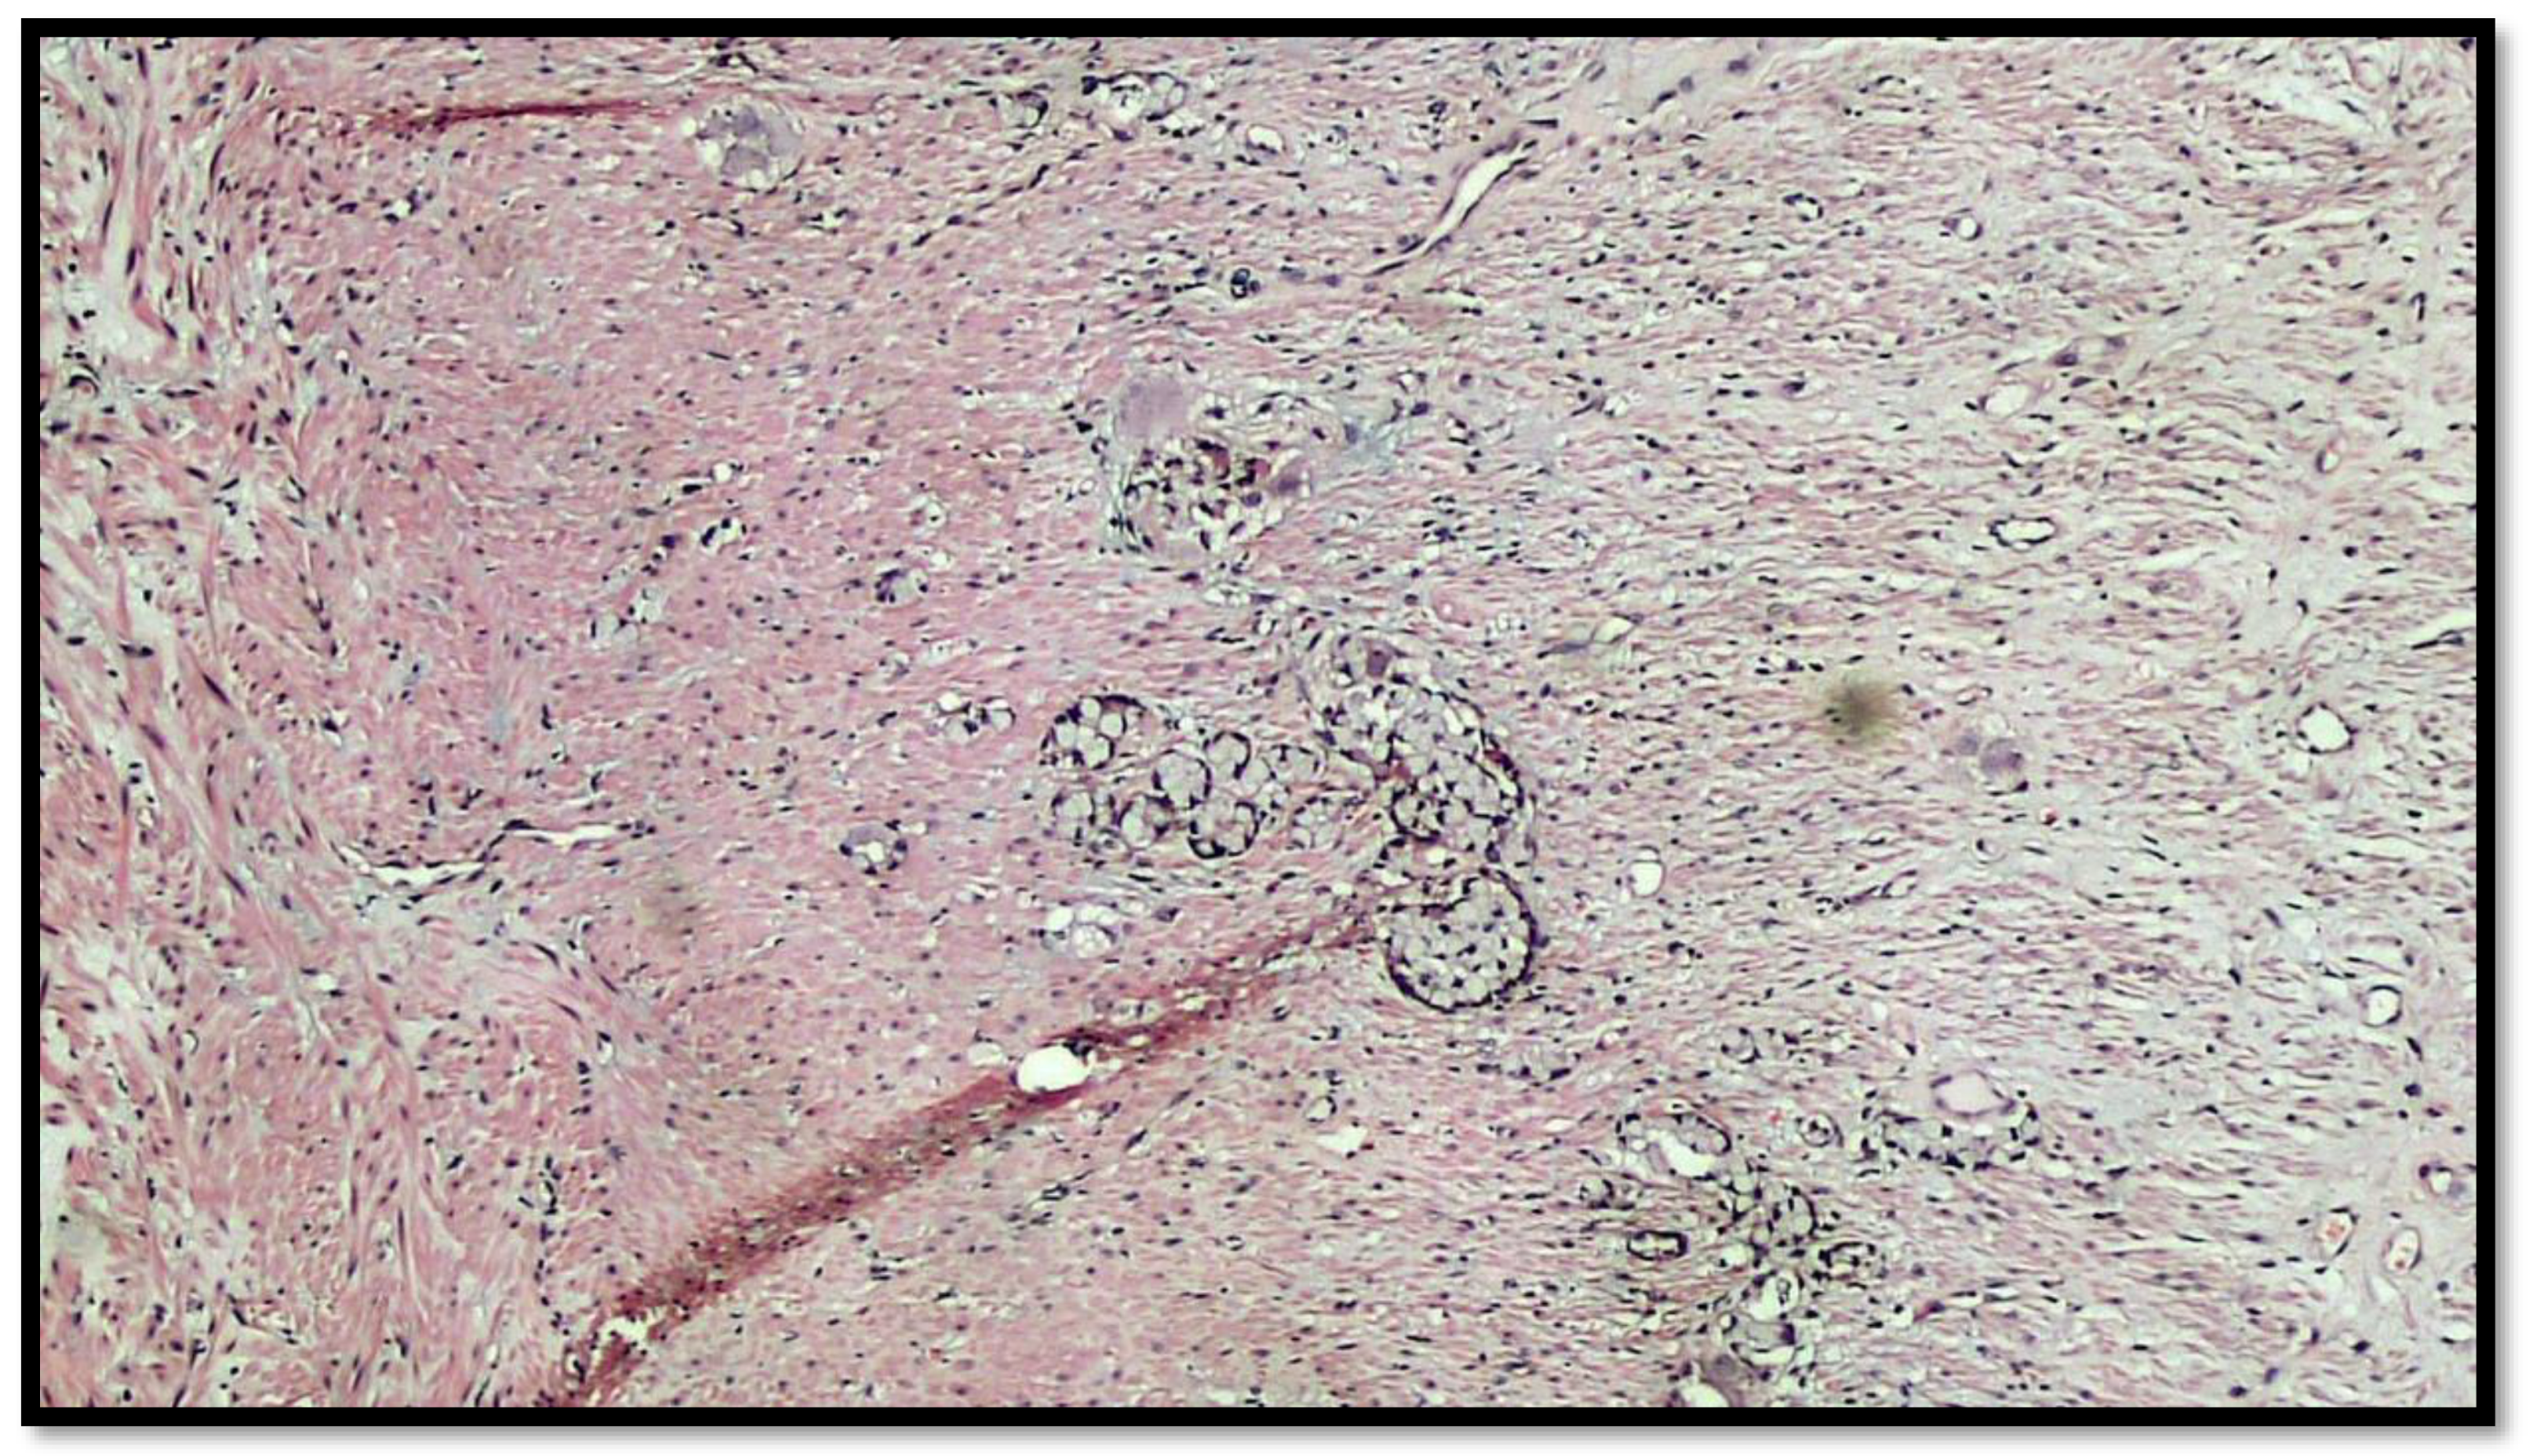

Figure 4.

Details of muscular invasion by GCC of the appendix (hematoxylin–eosin, original magnification 20×).